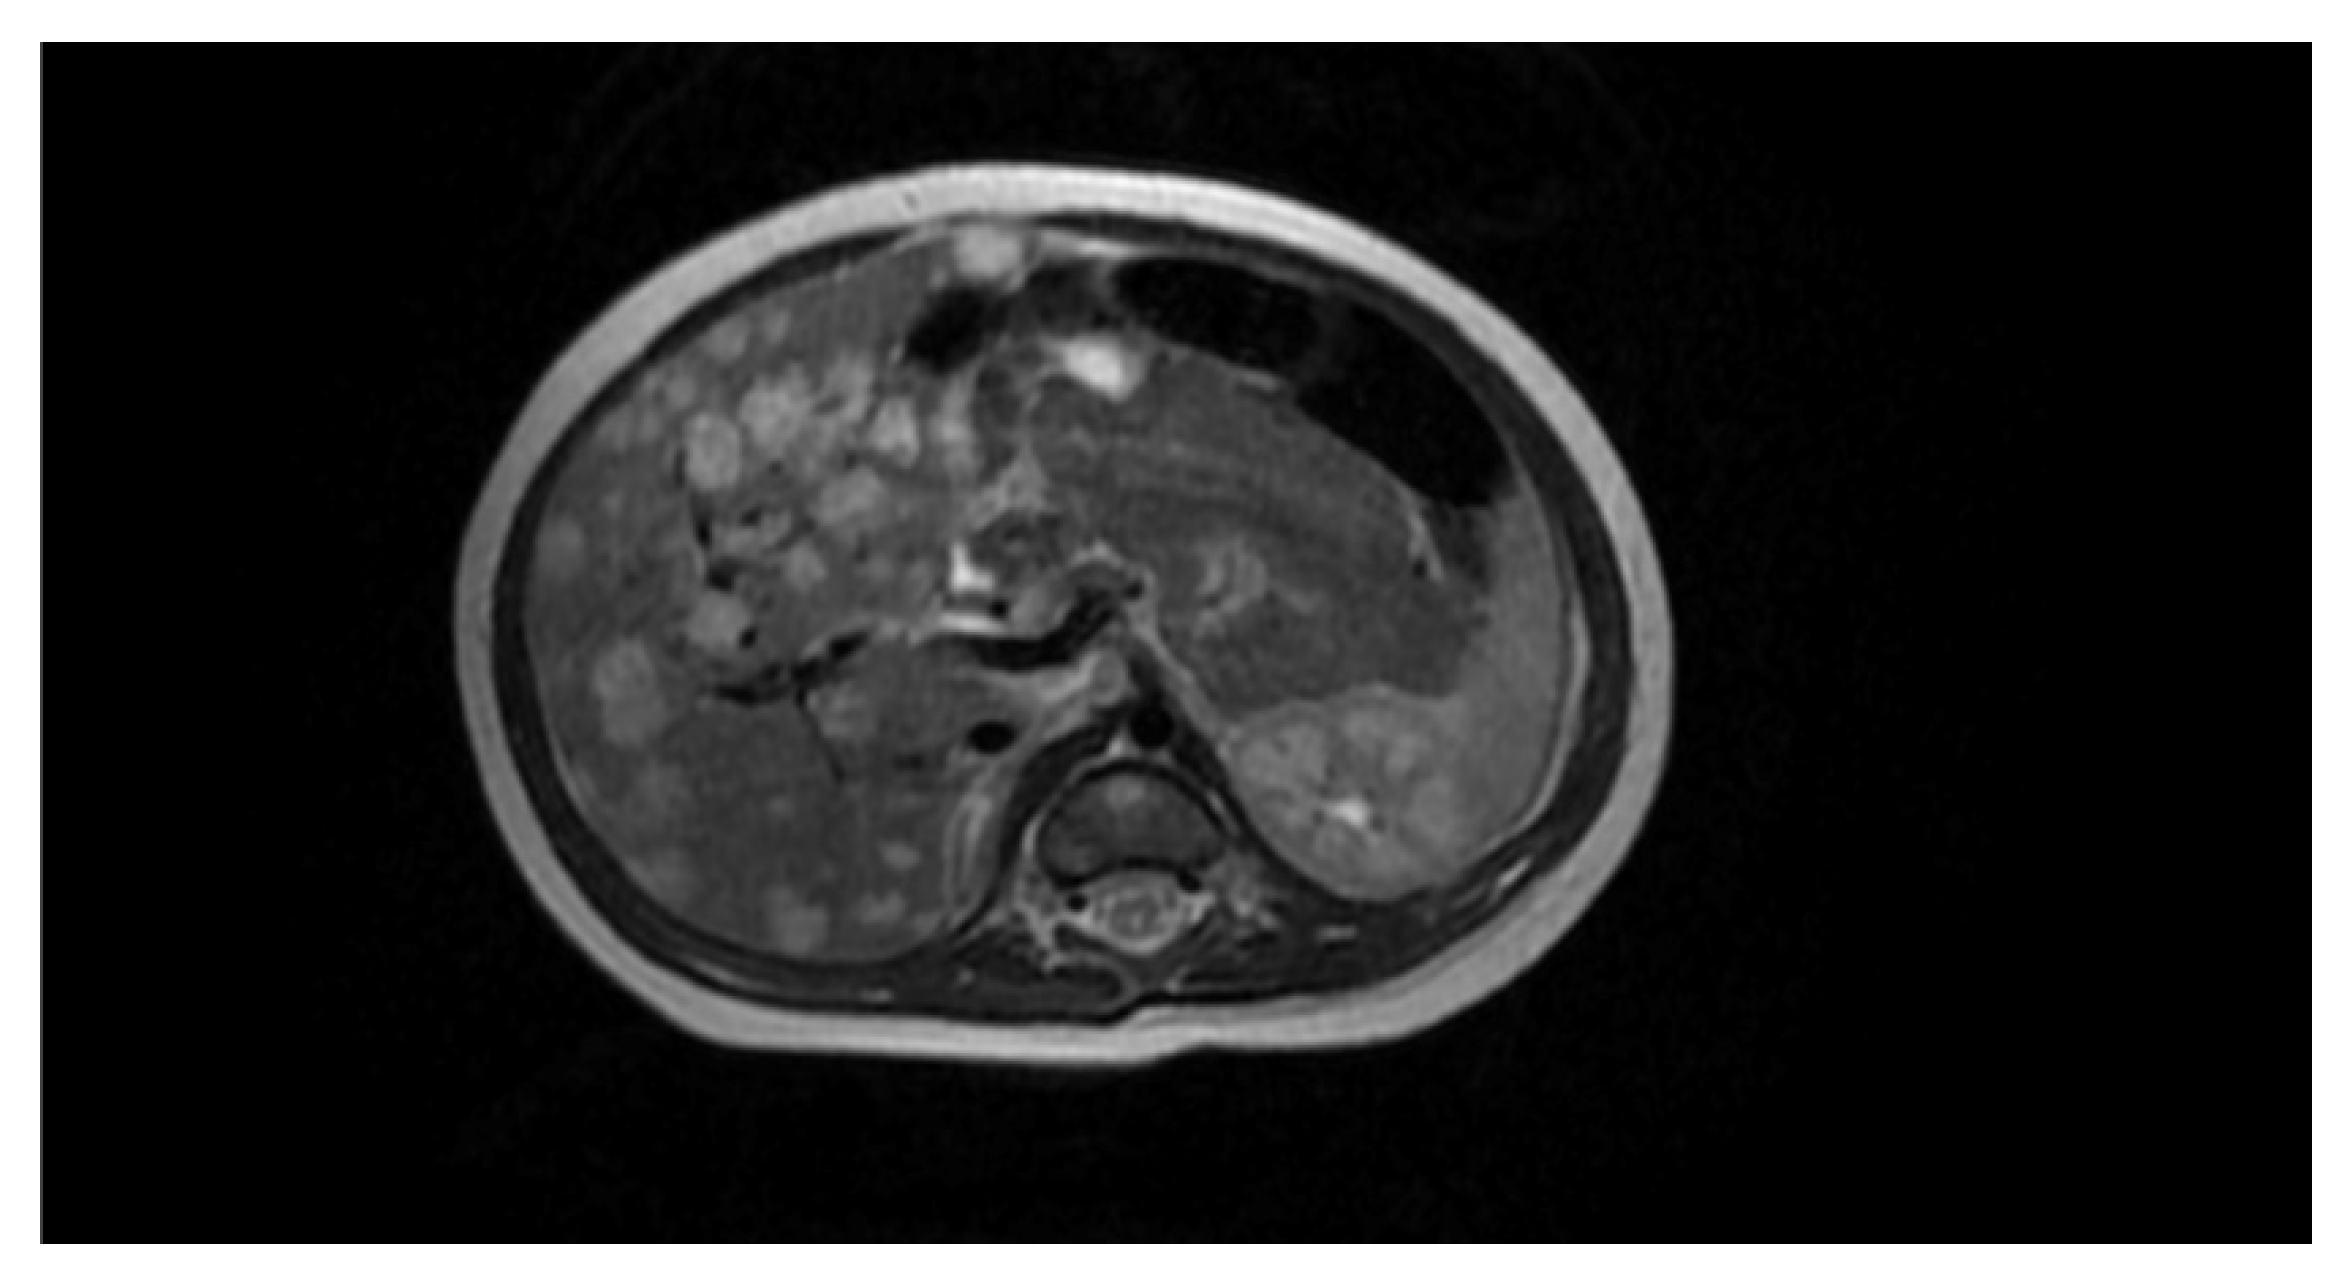

Preprints 73814 g002

Figure 1. Normal image of the abdominal organs.

Preprints 73814 g001

A boy from pregnancy II, delivery I, was born at the 30th week of gestation. The respiratory distress syndrome was identified in history and the neonate was diagnosed and treated at the Neonatal Intensive Care Unit. Cranial ultrasound scan (CrUSS) revealed status post grade II haemorrhage on the right side. A series of ultrasound examinations, performed at bedside at the Neonatal Intensive Care Unit, demonstrated normal images of the abdominal organs (see Figure 1)—the US examination was performed four times on day 3, 17, 24 and 40 of the baby’s life.